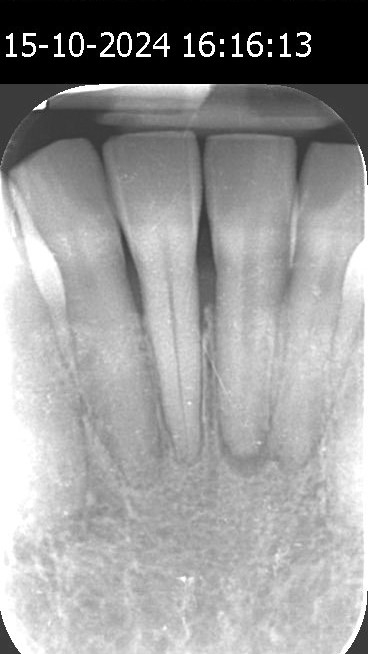

Nach einer Reihe von Healozon-Behandlungen berichtete die Patientin jedoch keine Beschwerden mehr. Die zunächst lockeren Zähne sind wieder fest im Kiefer verankert. Röntgenaufnahmen vom 15. Oktober 2024 zeigen eine deutliche Heilung des Kieferknochens und eine verbesserte Zahnknochendichte.

Vorher Nachher